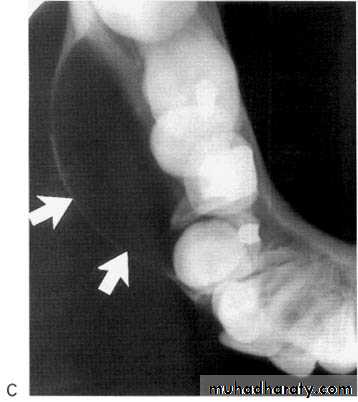

Inferior Alveolar Nerve Canal and Mental Foramen